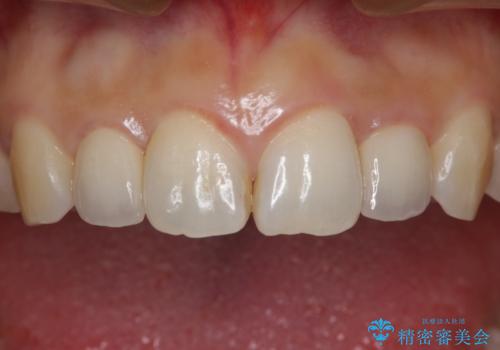

歯科技工士さんとの打ち合わせを重ね、周囲の歯としっかりなじむ天然歯のような被せ物をお作りすることが出来ました。

矯正治療と補綴治療をうまく組み合わせることで、美しい口元に仕上げることが出来ました。矯正治療、補綴治療をまとめて行える総合歯科治療を体現した治療といえます。